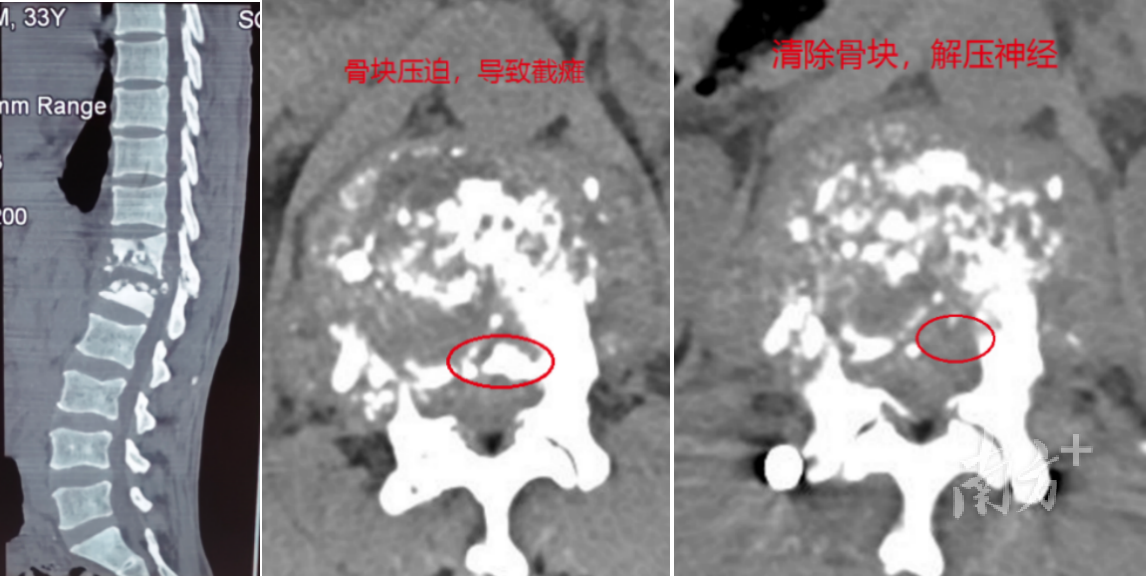

患者术前术后胸部CT对比。

经过仔细查抄后,中山大学孙逸仙挂牵病院脊柱外科援藏群众胡旭民判断,阿措是由于胸椎结核的破碎压迫脊髓,出现截瘫症状,并决定立即执行胸椎内镜手术。